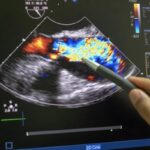

1. Ultrassonografia escrotal com doppler

É o principal exame de imagem para avaliar varicocele, cistos e inflamações nos testículos e epidídimos. O doppler analisa o fluxo sanguíneo, identificando alterações que podem comprometer a produção e a qualidade dos espermatozoides.